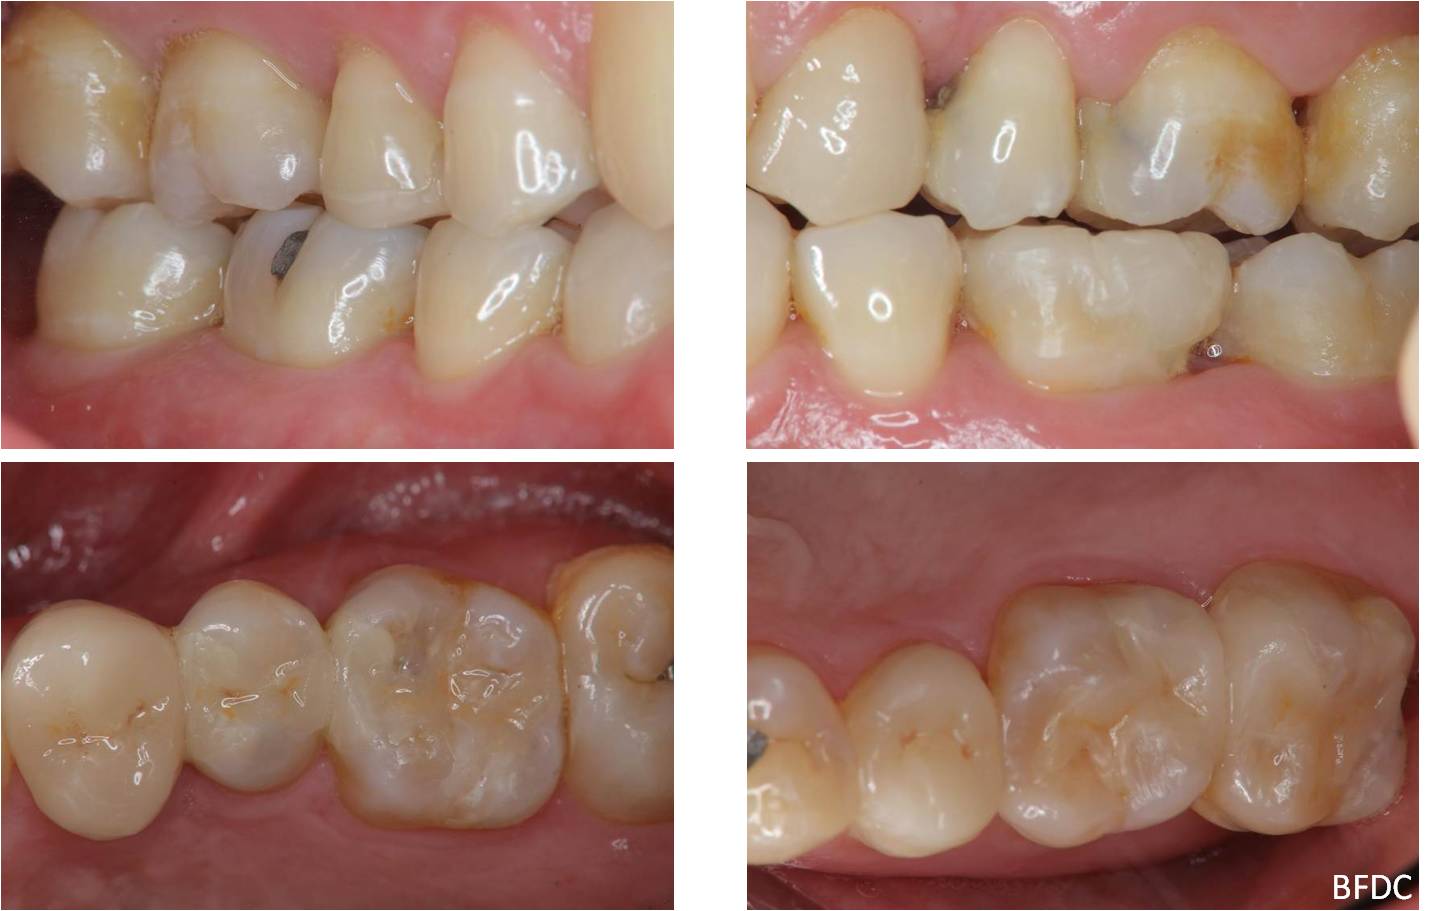

陶瓷崁體及冠蓋體-蛀牙-#1516172526 大範圍的補皮,該如何選擇,嵌體的方式就適用於大範圍的填補,因為它是一體成形, 嵌體材質多種,以往才會使用黃金合金,但因價格昂貴且顏色太過突出,因此現在多使用玻璃陶瓷二氧化鋯等材質的全瓷冠。嵌體有其優勢,因一體成形的材料,硬度和穩定性都較高,不用一點一點填補,減少下方凹陷重複蛀牙的危機,也不會變形或染色,美觀度高很多。 #1516172526蛀牙 #1516172526蛀牙 崁體及冠蓋體修形 安裝模型至咬合器 嵌體及冠塊體製作 陶瓷崁體及冠蓋體 黏著後 黏著後X光 術前、術後比較 嵌體有其優勢,因一體成形的材料,硬度和穩定性都較高,不用一點一點填補,減少下方凹陷重複蛀牙的危機,也不會變形或染色,美觀度高很多。

能避免片狀樹脂造成的,下方重複蛀牙,或彈性大造成咬合不舒服的問題,若有多顆牙齒填補,或坑陷較大者,如牙齒已蛀超過1/2或2/3者,才建議使用此種方式。